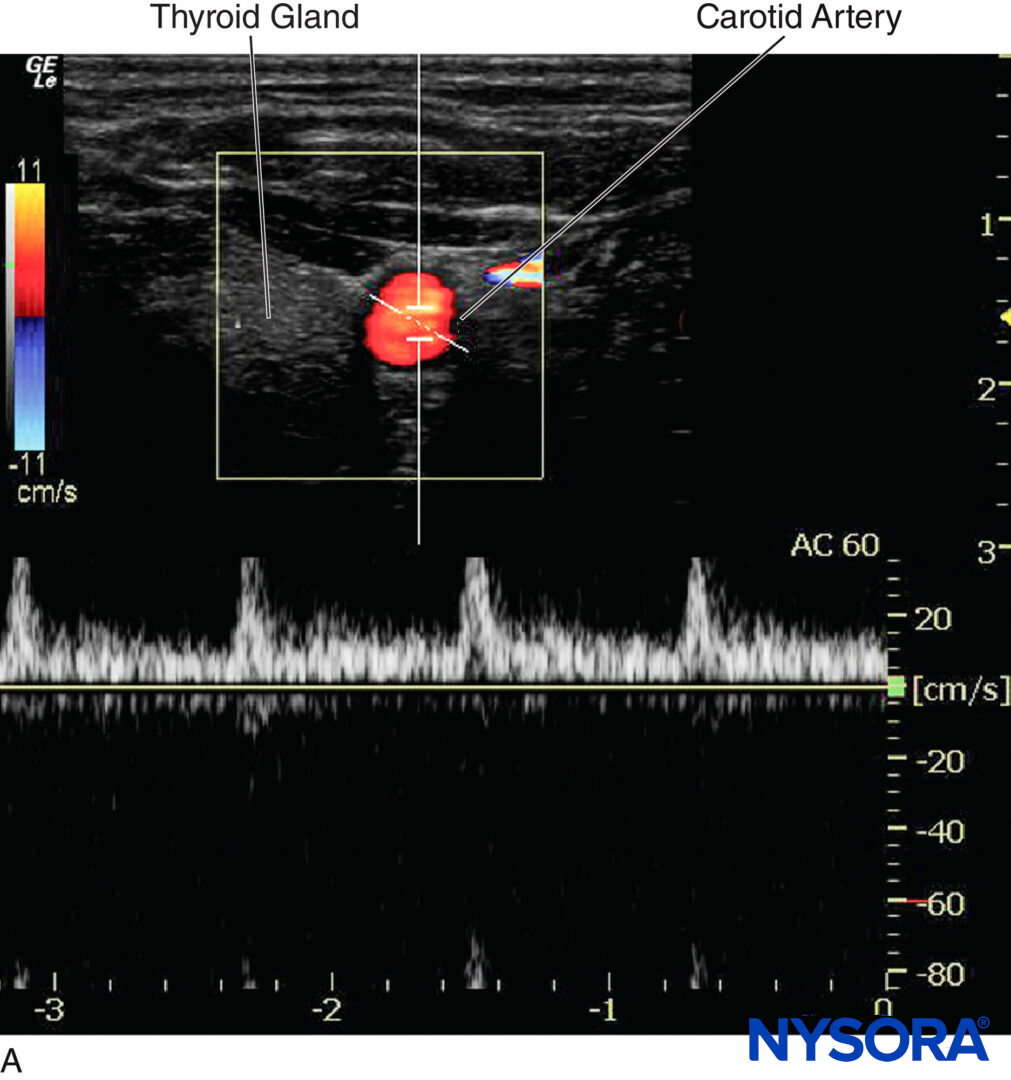

Color Doppler produces a color-coded map of Doppler shifts superimposed onto a B-mode ultrasound image. Blood flow direction depends on whether the motion is toward or away from the transducer. Selected by convention, red and blue colors provide information about the direction and velocity of the blood flow. According to the color map (color bar) in the upper left-hand corner of the figure (Figure 12), the red color on the top of the bar denotes the flow coming toward the ultrasound probe, and the blue color on the bottom of the bar indicates the flow away from the probe.

B-mode ultrasound image. Selected by convention, red and blue colors provide information about the direction and velocity of the blood flow. (Adapted with permission from Hadzic A: Hadzic’s Peripheral Nerve Blocks and Anatomy for Ultrasound-Guided Regional Anesthesia, 2nd ed. New York: McGraw-Hill, Inc; 2011.)

Figure 13. Color Doppler mode is used to detect the direction of the blood vessel.

In ultrasound-guided peripheral nerve blocks, color Doppler mode is used to detect the presence and nature of the blood vessels (artery vs. vein) in the area of interest. When the direction of the ultrasound beam changes, the color of the arterial flow switches from blue to red, or vice versa, depending on the convention used (Figures 13, 14A, 14B, and 14C). Power Doppler is up to five times more sensitive in detecting blood flow than color Doppler, and it is less dependent on the scanning angle. Thus, power Doppler can be used to identify the smaller blood vessels more reliably. The drawback is that power Doppler does not provide any information on the direction and speed of blood flow (Figure 15).

Figure 14. A: Carotid artery displays a red color when the blood flows toward the transducer. B: Carotid artery displays ambiguous color at a 90° Doppler angle; the equal waveform can be seen on both sides of the baseline. C: Carotid artery displays blue color when the blood flows away from the transducer.